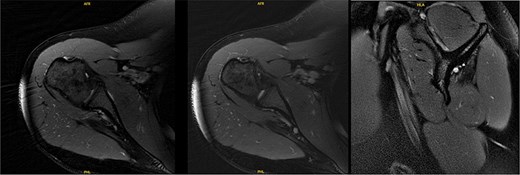

An 18-year-old, right-hand dominant woman presented reporting several weeks of right shoulder pain limiting participation in DIII collegiate volleyball. Examination revealed atrophy of the infraspinatus region. Muscle testing revealed weakness of infraspinatus and supraspinatus with reproducible symptoms. Radiographs were without transverse scapular ligament calcification (Fig. 1). Magnetic resonance imaging (MRI) arthrogram revealed low-grade undersurface fraying of the supraspinatus and infraspinatus tendons consistent with impingement, hypertrophic posterior inferior labrum, and no evidence of paralabral cyst (Fig. 2). Rest from hitting activities, anti-inflammatory medications, and periscapular strengthening therapy were initiated.

Radiographic imaging on initial presentation was without transverse scapular ligament calcification.

Initial MRI arthrogram revealed low-grade undersurface fraying of the supraspinatus and infraspinatus tendons consistent with internal impingement, hypertrophic posterior inferior labrum without visible tearing, and no evidence of paralabral cyst.